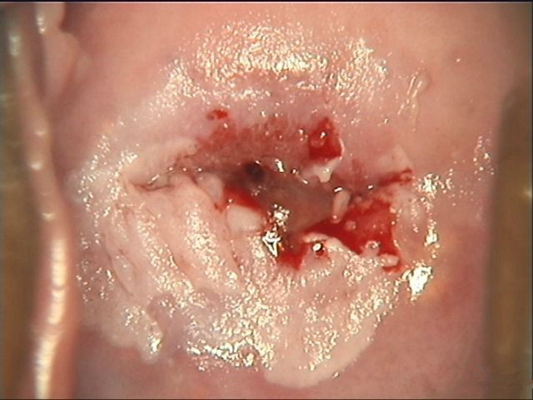

子宮頸糜爛圖片

宮頸糜爛 (56)